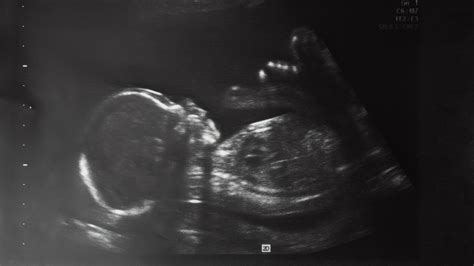

Reaching the halfway mark of your pregnancy is a monumental milestone that often brings a mix of excitement and nervous anticipation. As you settle into your second trimester, you are likely preparing for one of the most significant medical appointments of your entire journey: the 20 weeks pregnant ultrasound. Also known as the anatomy scan or the morphology scan, this comprehensive examination is designed to take a detailed look at your growing baby’s development from head to toe. It is a moment where the reality of parenthood truly begins to sink in as you see your little one’s features, movements, and heartbeat in stunning detail on the screen.

The 20 weeks pregnant ultrasound is a routine diagnostic scan typically performed between 18 and 22 weeks of gestation. Unlike earlier, smaller scans that primarily confirmed the pregnancy and measured the crown-rump length, this appointment is far more thorough. Its primary purpose is to ensure that your baby is developing at a healthy rate and that all major organs and systems are functioning as expected.

During this session, a highly trained sonographer will methodically examine your baby’s anatomy. This process helps your healthcare provider identify any potential health concerns early on and provides peace of mind regarding the structural integrity of your baby’s development. It is also the appointment where, if you choose, you may be able to find out the biological sex of your baby, provided the baby is in a cooperative position during the scan.

The anatomy scan is a transformative moment that bridges the gap between feeling the flutters of movement and seeing the reality of your child. As you view the screen, you might see them yawning, sucking their thumb, or practicing their kicking. These small, fleeting moments are the foundation of your early bond. Once you leave the clinic, you will likely walk away with a set of grainy but precious photos that will serve as the very first addition to your baby’s photo album. Take the time to process this experience, celebrate the health of your baby, and look forward to the remaining months of your journey toward welcoming your little one into the world.